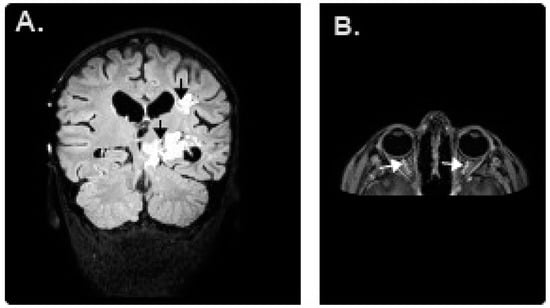

2. Case Presentation